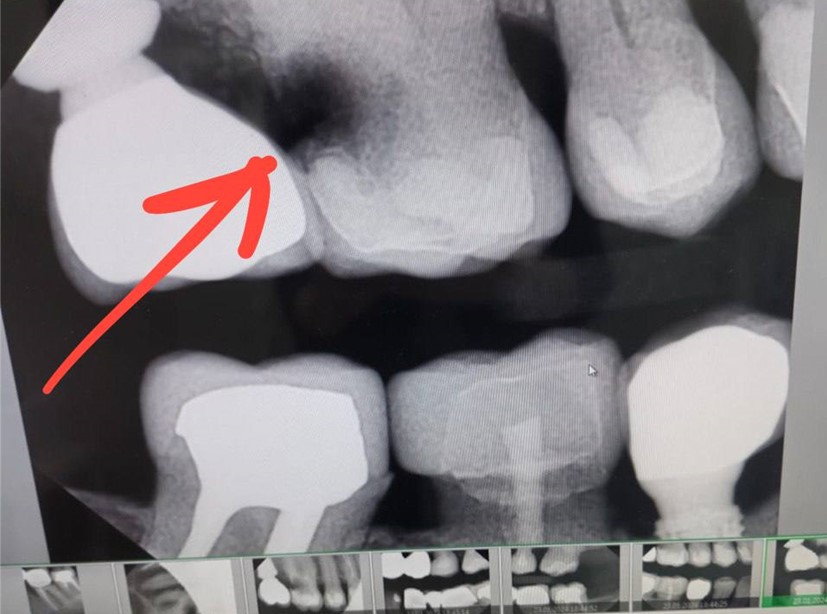

А вот такие снимки нам могут прислать пациенты, с опасением, что выпал имплантат. В действительности, это повреждение ремонтопригодной супраструктуры имплантата. Сам он на месте.